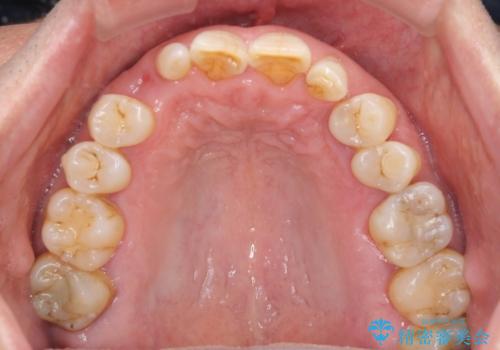

- 乳歯や矮小歯が多くある前歯部の審美障害が気にして来院された患者様です。

上顎の矮小歯は隙間が多く、歯軸の傾斜も大きかったため、部分矯正により補綴治療前に歯の位置を整えることとしました。

下顎の乳歯は支台歯として機能することは困難と思われたので、事前に抜歯をし、上顎の矯正治療終了のタイミングに合わせて、セラミックブリッジにて補綴治療することとしました。